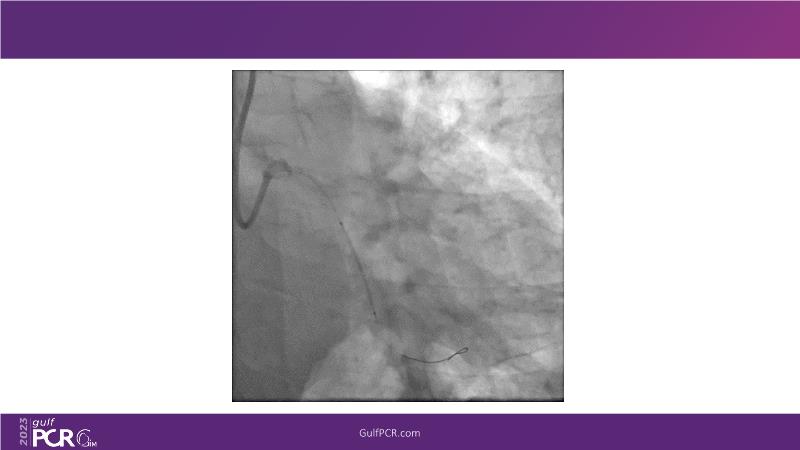

This session is a valuable resource for grasping innovative strategies in handling bifurcation and extended diffuse lesions through dedicated stenting solutions. Explore insights into the advanced Myval next-generation THV technology, unveiling its distinctive features, procedural advantages, and clinical outcomes across a diverse patient pool. Gain understanding into the CorAlign technique, ensuring accurate commissural and coronary alignment while maintaining coronary access. Additionally, delve into the techniques for precise sizing, positioning, and deploying of Myval THV.

- To understand the technique of precise sizing, positioning and deployment of Myval THV